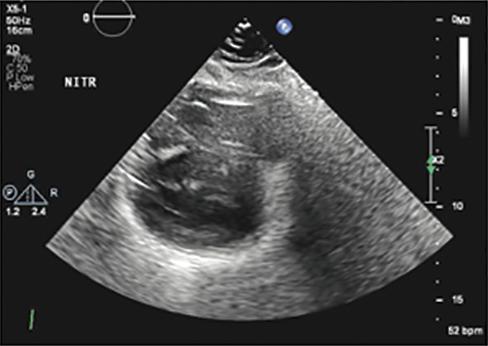

Imaging in Heart Failure with Preserved Ejection Fraction: A Multimodality Imaging Point of View

Serkan Ünlü, Özge Özden and Ahmet Çelik

Role of Imaging in Cardiomyopathies

Vincenzo Castiglione, Alberto Aimo, Giancarlo Todiere, Andrea Barison, Iacopo Fabiani, Giorgia Panichella, Dario Genovesi, Lucrezia Bonino Alberto Clemente, Filippo Cademartiri, Alberto Giannoni, Claudio Passino, Michele Emdin and Giuseppe Vergaro

DOI: https://doi.org/10.15420/cfr.2022.26